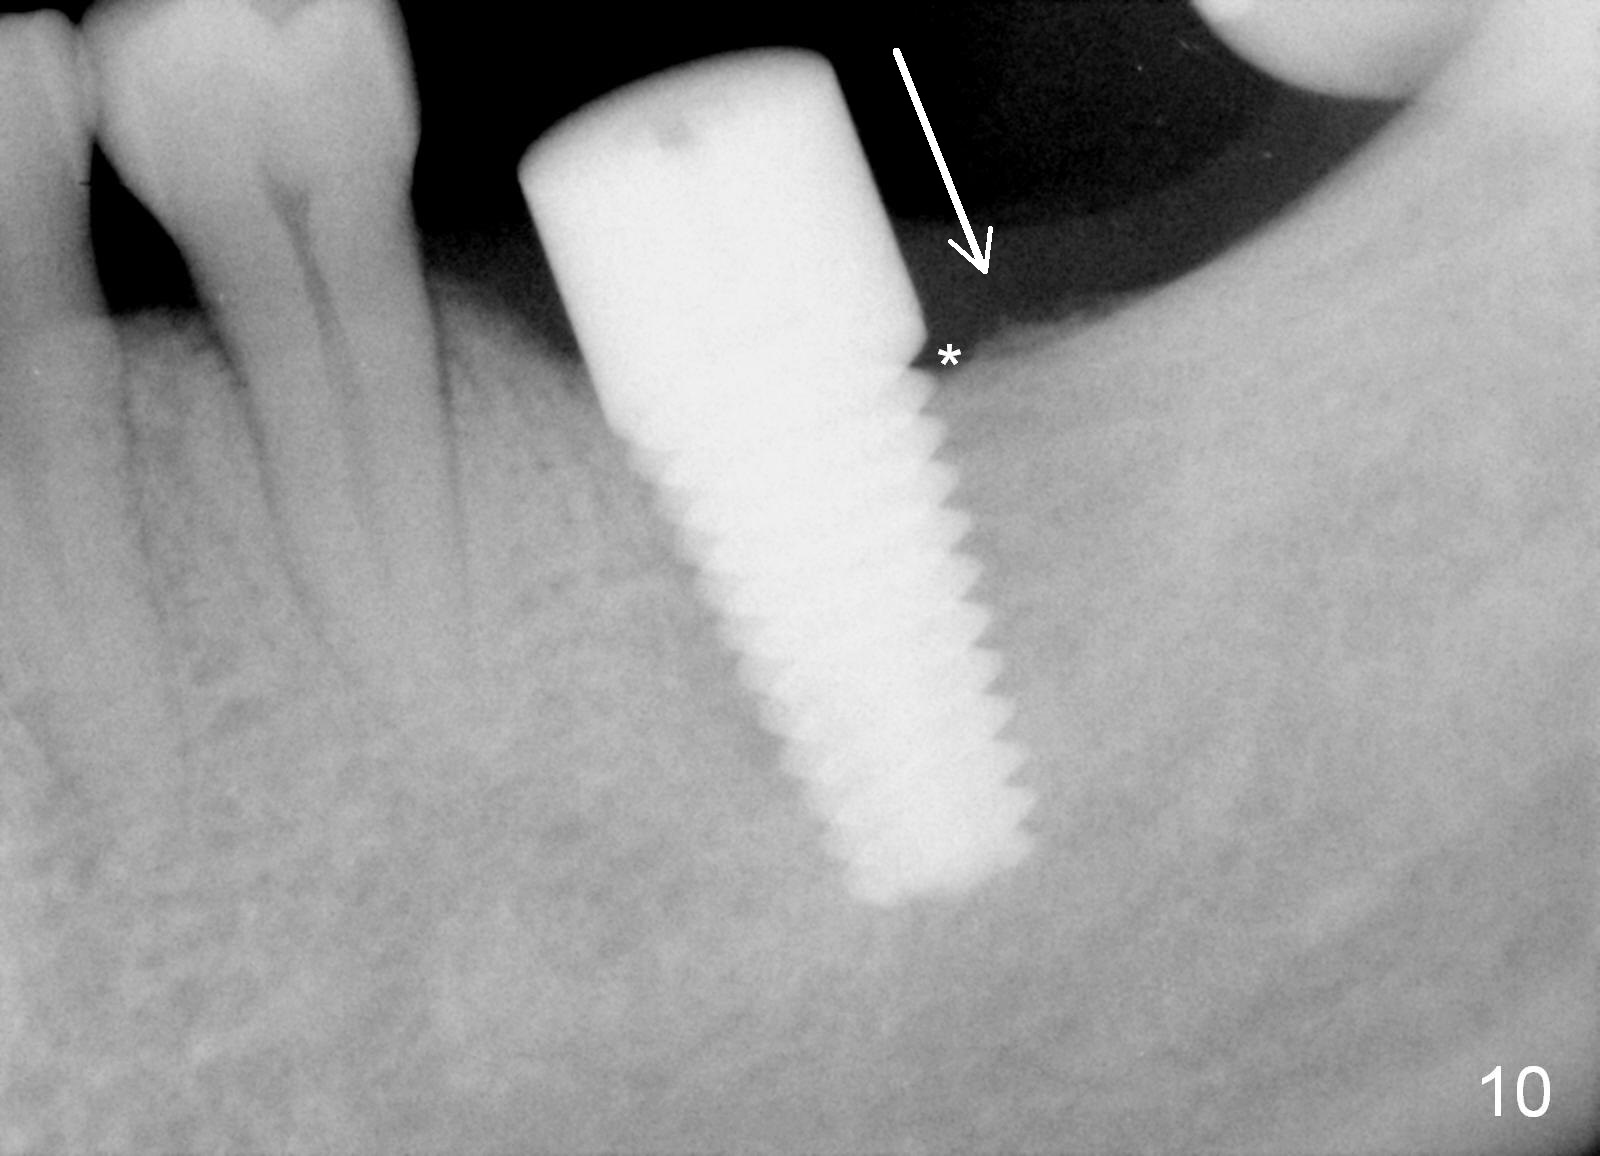

The implant is placed in the mesial socket (Fig.9 T: 7x17 mm tap): the mesial space is being obliterated (>), while the distal one (D) should have been filled with bone graft and the overlying gingiva is approximated with suture (Fig.6). Bone graft is not placed, because graft may increase chance of infection. In fact this assumption is wrong. First, when the tooth #8 is extracted a few months later, bone graft is done with immediate implant. No infection occurs. Second, no bone graft in #18 distal socket leads to gingival recession, as shown below.

The patient returns for #19 restoration one year postop. The distal coronal threads appear not covered by bone (Fig.10 *) with distobuccal gingival recession (Fig.11). The buccal bulging (Fig.11 arrowheads) may be related to thin or no buccal plate. Bone graft at time of immediate implant may decrease the likelihood. In addition, the implant is placed buccally slightly (Fig.12). The gingival recession appears to have decreased 1 year 9 months post cementation (Fig.13). A thick keratinized gingiva forms around the implant at #8 1 year 11 months post cementation. There seems to be no bone loss 2.5 years post cementation (Fig.14,15, as compared to Fig.10)